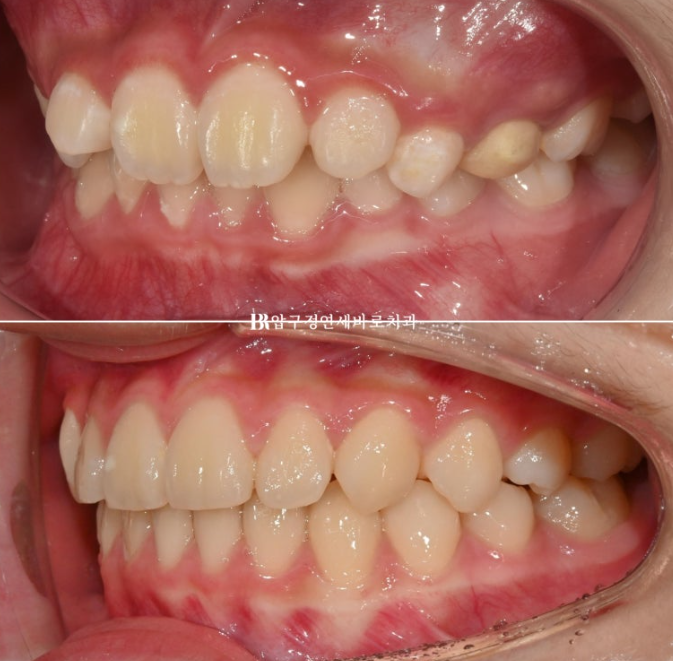

어금니 교합은 1급 교합관계를 보입니다.

24.09

배열도 좋습니다.

전 후 비교 사진 보겠습니다.

2022.09~2024.09

중심선은 잘 맞았고 앞니가 깊게 물리는 과개교합도 개선이 되었습니다.